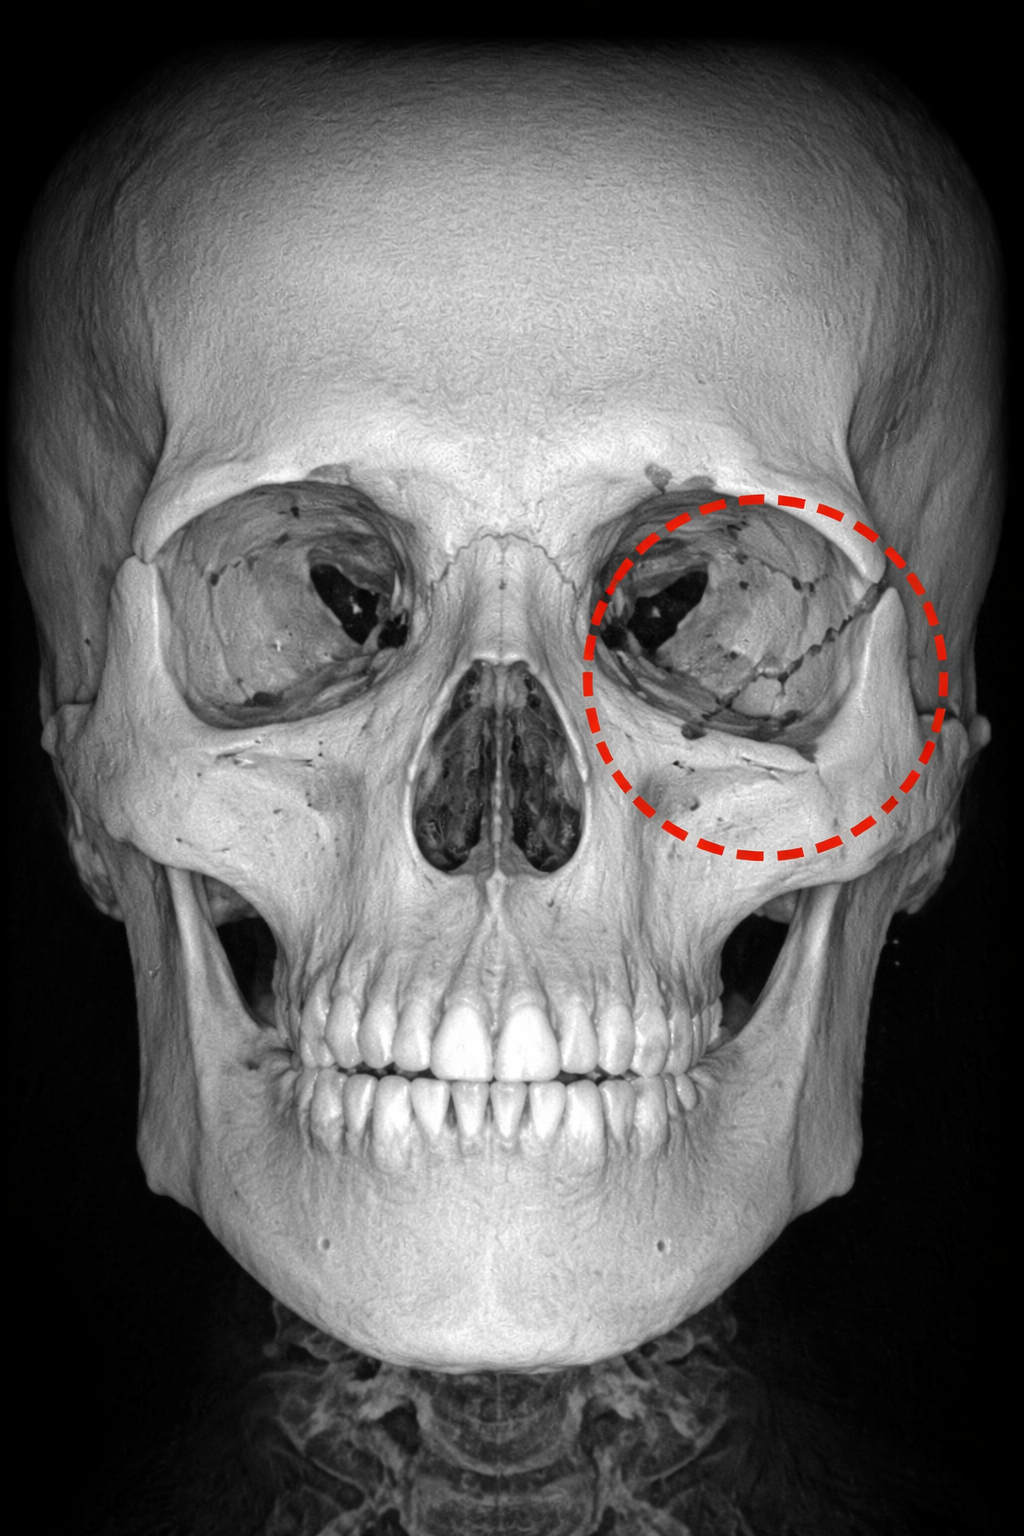

Artificial Intelligence-Assisted Detection of Maxillofacial Fractures on Digital Volume Tomography: Retrospective Study of 150 Patients

Yildirim A., Hertach R., and Yildirim V.

This retrospective study evaluated a deep learning-based AI model for detecting maxillofacial fractures on Digital Volume Tomography (DVT) in 150 patients. The AI achieved near-perfect accuracy (98%) and outperformed junior clinicians, while matching the performance of senior experts. These findings highlight AI’s potential to accelerate diagnosis, reduce missed fractures, and improve emergency trauma care workflows.